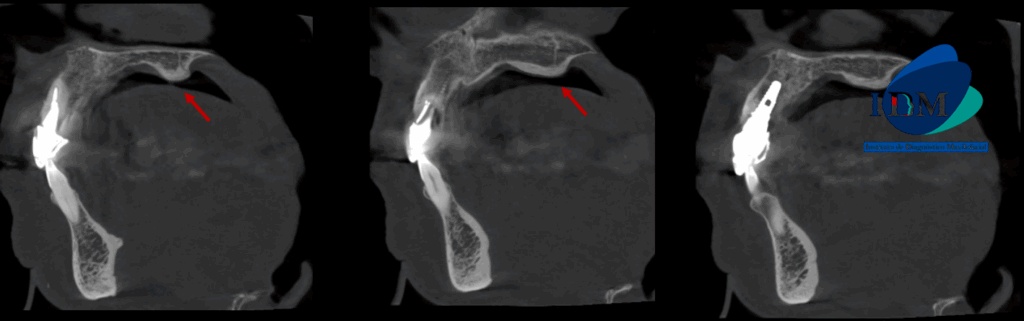

A la evaluación de la tomografía volumétrica (cone beam) bimaxilar en los cortes axiales (Figura 2) y transaxiales (Figura 3) se observa imagen hiperdensa de densidad ósea y forma bilobular localizada en en zona de paladar duro a nivel de línea media

CORTES SAGITALES

- Torus palatino

El TP se identifica con frecuencia en la tomografía cone beam (TCBC) resultando muchas veces un hallazgo incidental, donde se presenta como una protuberancia ósea con una densidad similar a la del hueso compacto (1).